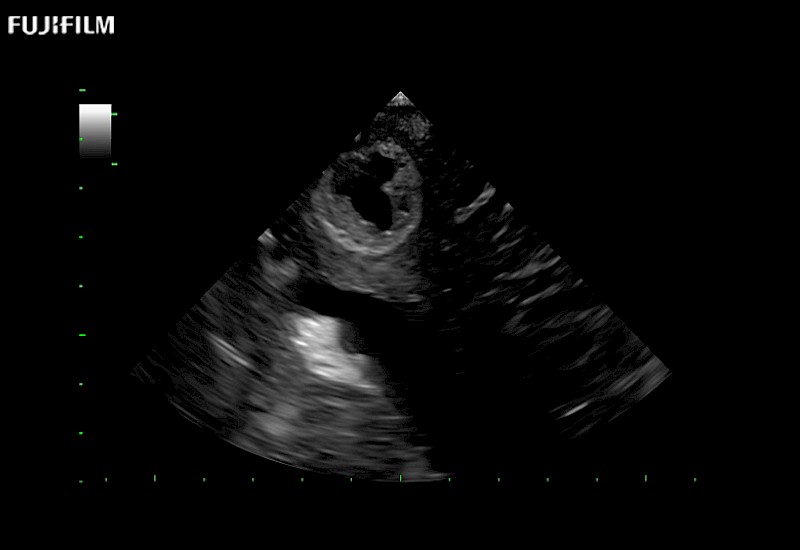

Tight curved (12mm) array transducer that is ideal for scanning during cranial guidance procedures.

Main Specifications:

Smaller footprint (20mm) curved array transducer that is ideal for scanning during cranial guidance procedures.